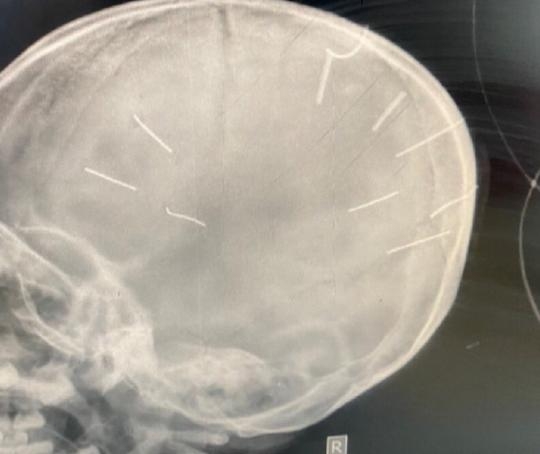

Hình chụp cắt lớp phát hiện hình ảnh giống đinh trong sọ

Ngay sau đó, các bác sĩ khoa cấp cứu đã chụp phim, làm chẩn đoán và phát hiện 9 dị vật giống đinh trong sọ não bé gái nên đã chuyển tuyến lên Bệnh viện đa khoa Xanh Pôn, đồng thời báo Công an huyện Thạch Thất.

Sau khi Bệnh viện Đa khoa Xanh Pôn tiến hành chụp cắt lớp, dựng hình đã nhận thấy có những hình ảnh giống như đinh gỗ ở sọ và tổ chức não của bé Đ.N.A.